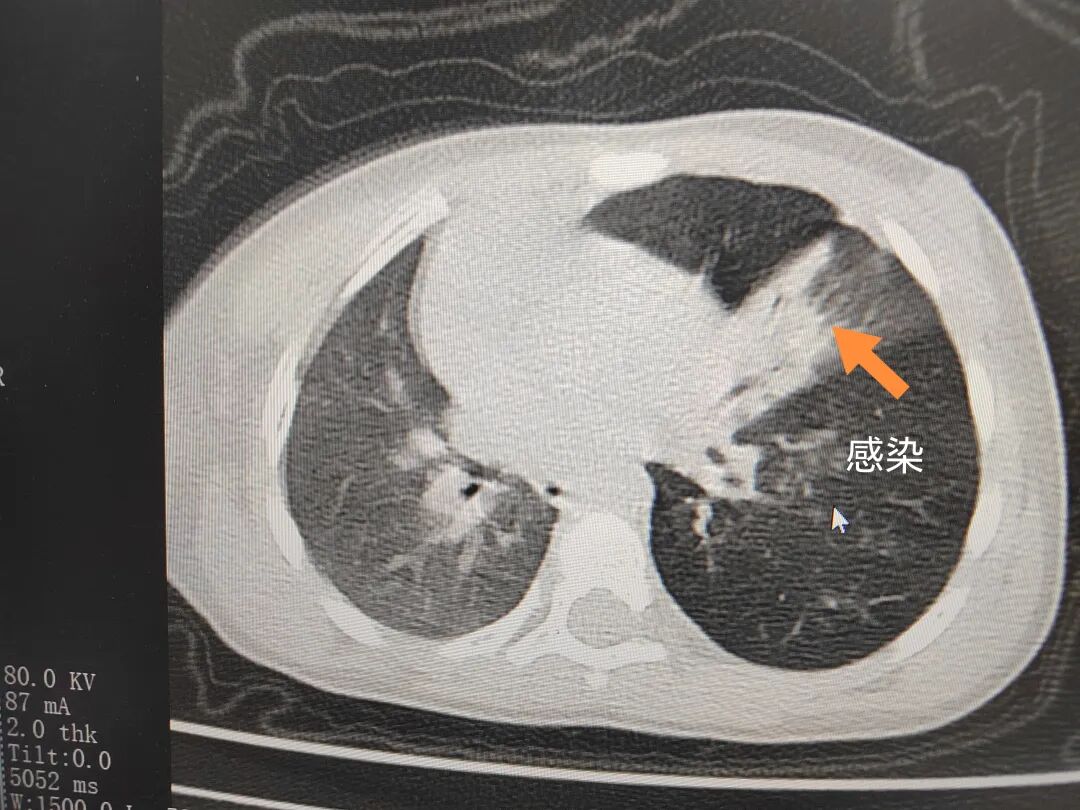

三天后(11月13日),趙寶出現(xiàn)高熱、咳喘加重,家長(zhǎng)著急了,再次帶他來(lái)到醫(yī)院。CT檢查顯示左肺過(guò)度充氣,左肺上下葉支氣管主干見(jiàn)不規(guī)則高密度影,左肺上葉可見(jiàn)大片狀密度增高影,縱隔窗實(shí)變,提示為“左側(cè)支氣管內(nèi)異物并繼發(fā)性改變,左肺上葉舌段肺膨脹不全”。

市二院小兒呼吸內(nèi)科團(tuán)隊(duì)迅速為患兒制定了周密的手術(shù)方案,并很快安排了氣管鏡探查。術(shù)中,主治醫(yī)師田慧等憑借嫻熟的氣管鏡操作技術(shù)成功將異物大塊板栗取出。由于板栗在氣管內(nèi)存留時(shí)間較長(zhǎng),質(zhì)地軟糯易碎,大大增加了手術(shù)難度。檢查還發(fā)現(xiàn),異物停留部位的氣管黏膜已出現(xiàn)充血紅腫、糜爛,導(dǎo)致患兒住院時(shí)間相應(yīng)延長(zhǎng)。此次事件給趙寶的家庭帶來(lái)了不小的驚嚇與擔(dān)憂,也再次為廣大家長(zhǎng)敲響了警鐘。